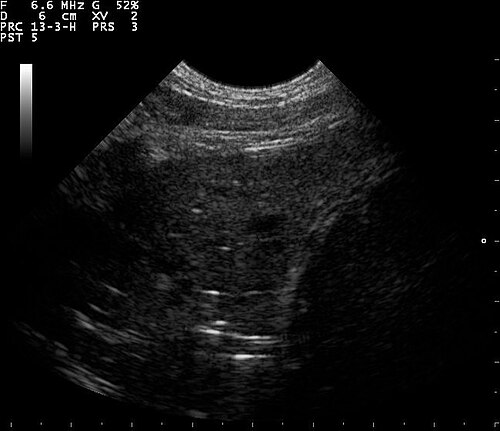

Lung Ultrasound — B-Lines (Pulmonary Fibrosis)

B-lines visible on lung ultrasound indicating interstitial disease in a patient with pulmonary fibrosis

ULTRASOUND Downloaded 2026-03-15

Ultrasound

B Mode

Wikimedia Commons: B lines on a lung ultrasound of a patient with fibrosis.jpg